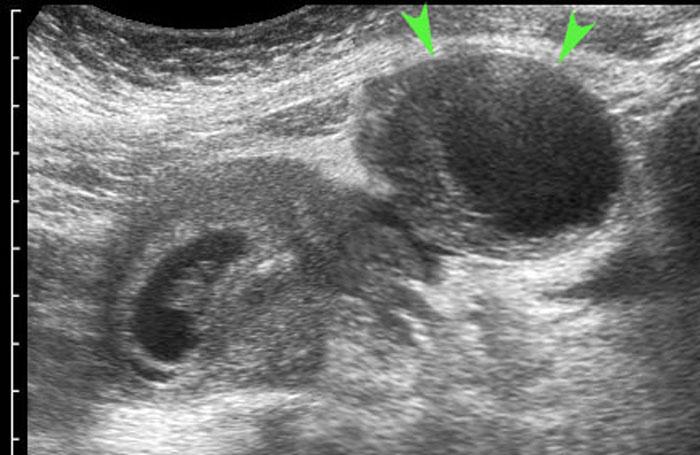

Ca lâm sàng 2

Ở người phụ nữ trẻ này với hai ngày đau hố chậu phải và CRP bằng 2, siêu âm phát hiện một nang buồng trứng bên phải thành mỏng.

Siêu âm đầu dò âm đạo (TVUS) cho thấy hình ảnh điển hình của các vách ngăn mỏng như ren, đồng thời thấy phần buồng trứng bình thường còn lại chứa các nang noãn bị “đẩy” sang một bên bởi nang xuất huyết.

Hình ảnh hoàn toàn bình thường sau 6 tuần.

Ca lâm sàng 5

Các nang xuất huyết tồn lưu thường chứa các khối đặc, không có mạch máu, không đồng nhất, đại diện cho cục máu đông.

Sự co rút của các cục máu đông này thường tạo ra các bờ lõm (đầu mũi tên).